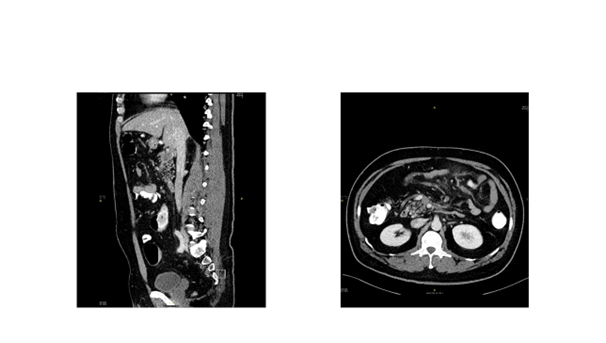

50-year-old gentleman previously healthy, non smoker, non alcoholic presents to Emergency Department (ED) with left hypochondrial colicky non radiating pain, aggravated by heavy meal for five days, and associated with severe diaphoresis and nausea. He sought for medical advice twice and treated first time as a case of gastritis, and on second visit basic blood work including CBC, U&E, Lactate, LFTs were within normal range and Ultrasound showed no abnormalities, and discharged on Paracetamol and antacids. Patient did not improve inspite of compliance with the prescribed medications and presented to our ED by the same complaints, on examination, patient was stable vitally, with soft non-tender abdomen and normal bowel sounds. He underwent comprehensive study including Ct abdomen with contrast which reveled: Thrombosis of the superior mesenteric vein and its branches noted. The thrombus is seen extending, through the main portal vein partially occluding its lumen, to involve the splenic vein and right portal vein as well (Figure 2). Enoxaparin was started for him, work up for thrombophilia was sent, GI consultation was made to arrange for OGD (Oesophago–gastro-Dudenoscopy), looking for malignancy which revealed erosive gastritis with significant modularity, CLO test was negative, tumor markers were sent (CA 125- CA19-9 CEA) were normal, homocysteine 13.9 (high), B12=111 (low), during his stay at hospital patient has no complain, and his physical exam was normal.

Patient discharged from hospital with diagnosis of homocystienemia, B12 deficiency, and normal thrombophilia work up. With plan to start rivaroxiban 20mg PO OD, frequent follow-up at clinic. After 6 month ct abdomen with contrast repeated and revealed recanalization of the portal vein and splenic vein with partially recanalization of the superior mesenteric vein which is surrounded with fat standing and multiple sub centimeter of lymph nodes.